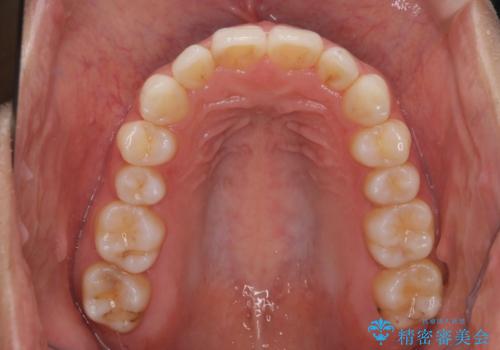

【インビザライン】前歯の後戻りを再矯正

- 前歯が出ていることを主訴に来院されました。検査の結果、口元が標準より出ているわけではなかったため今回はIPRと拡大をし、非抜歯で治療を行いました。

非抜歯でも歯軸の向きを改善したことで前歯が下がり、出っ歯に見えてしまうという主訴が改善しました。